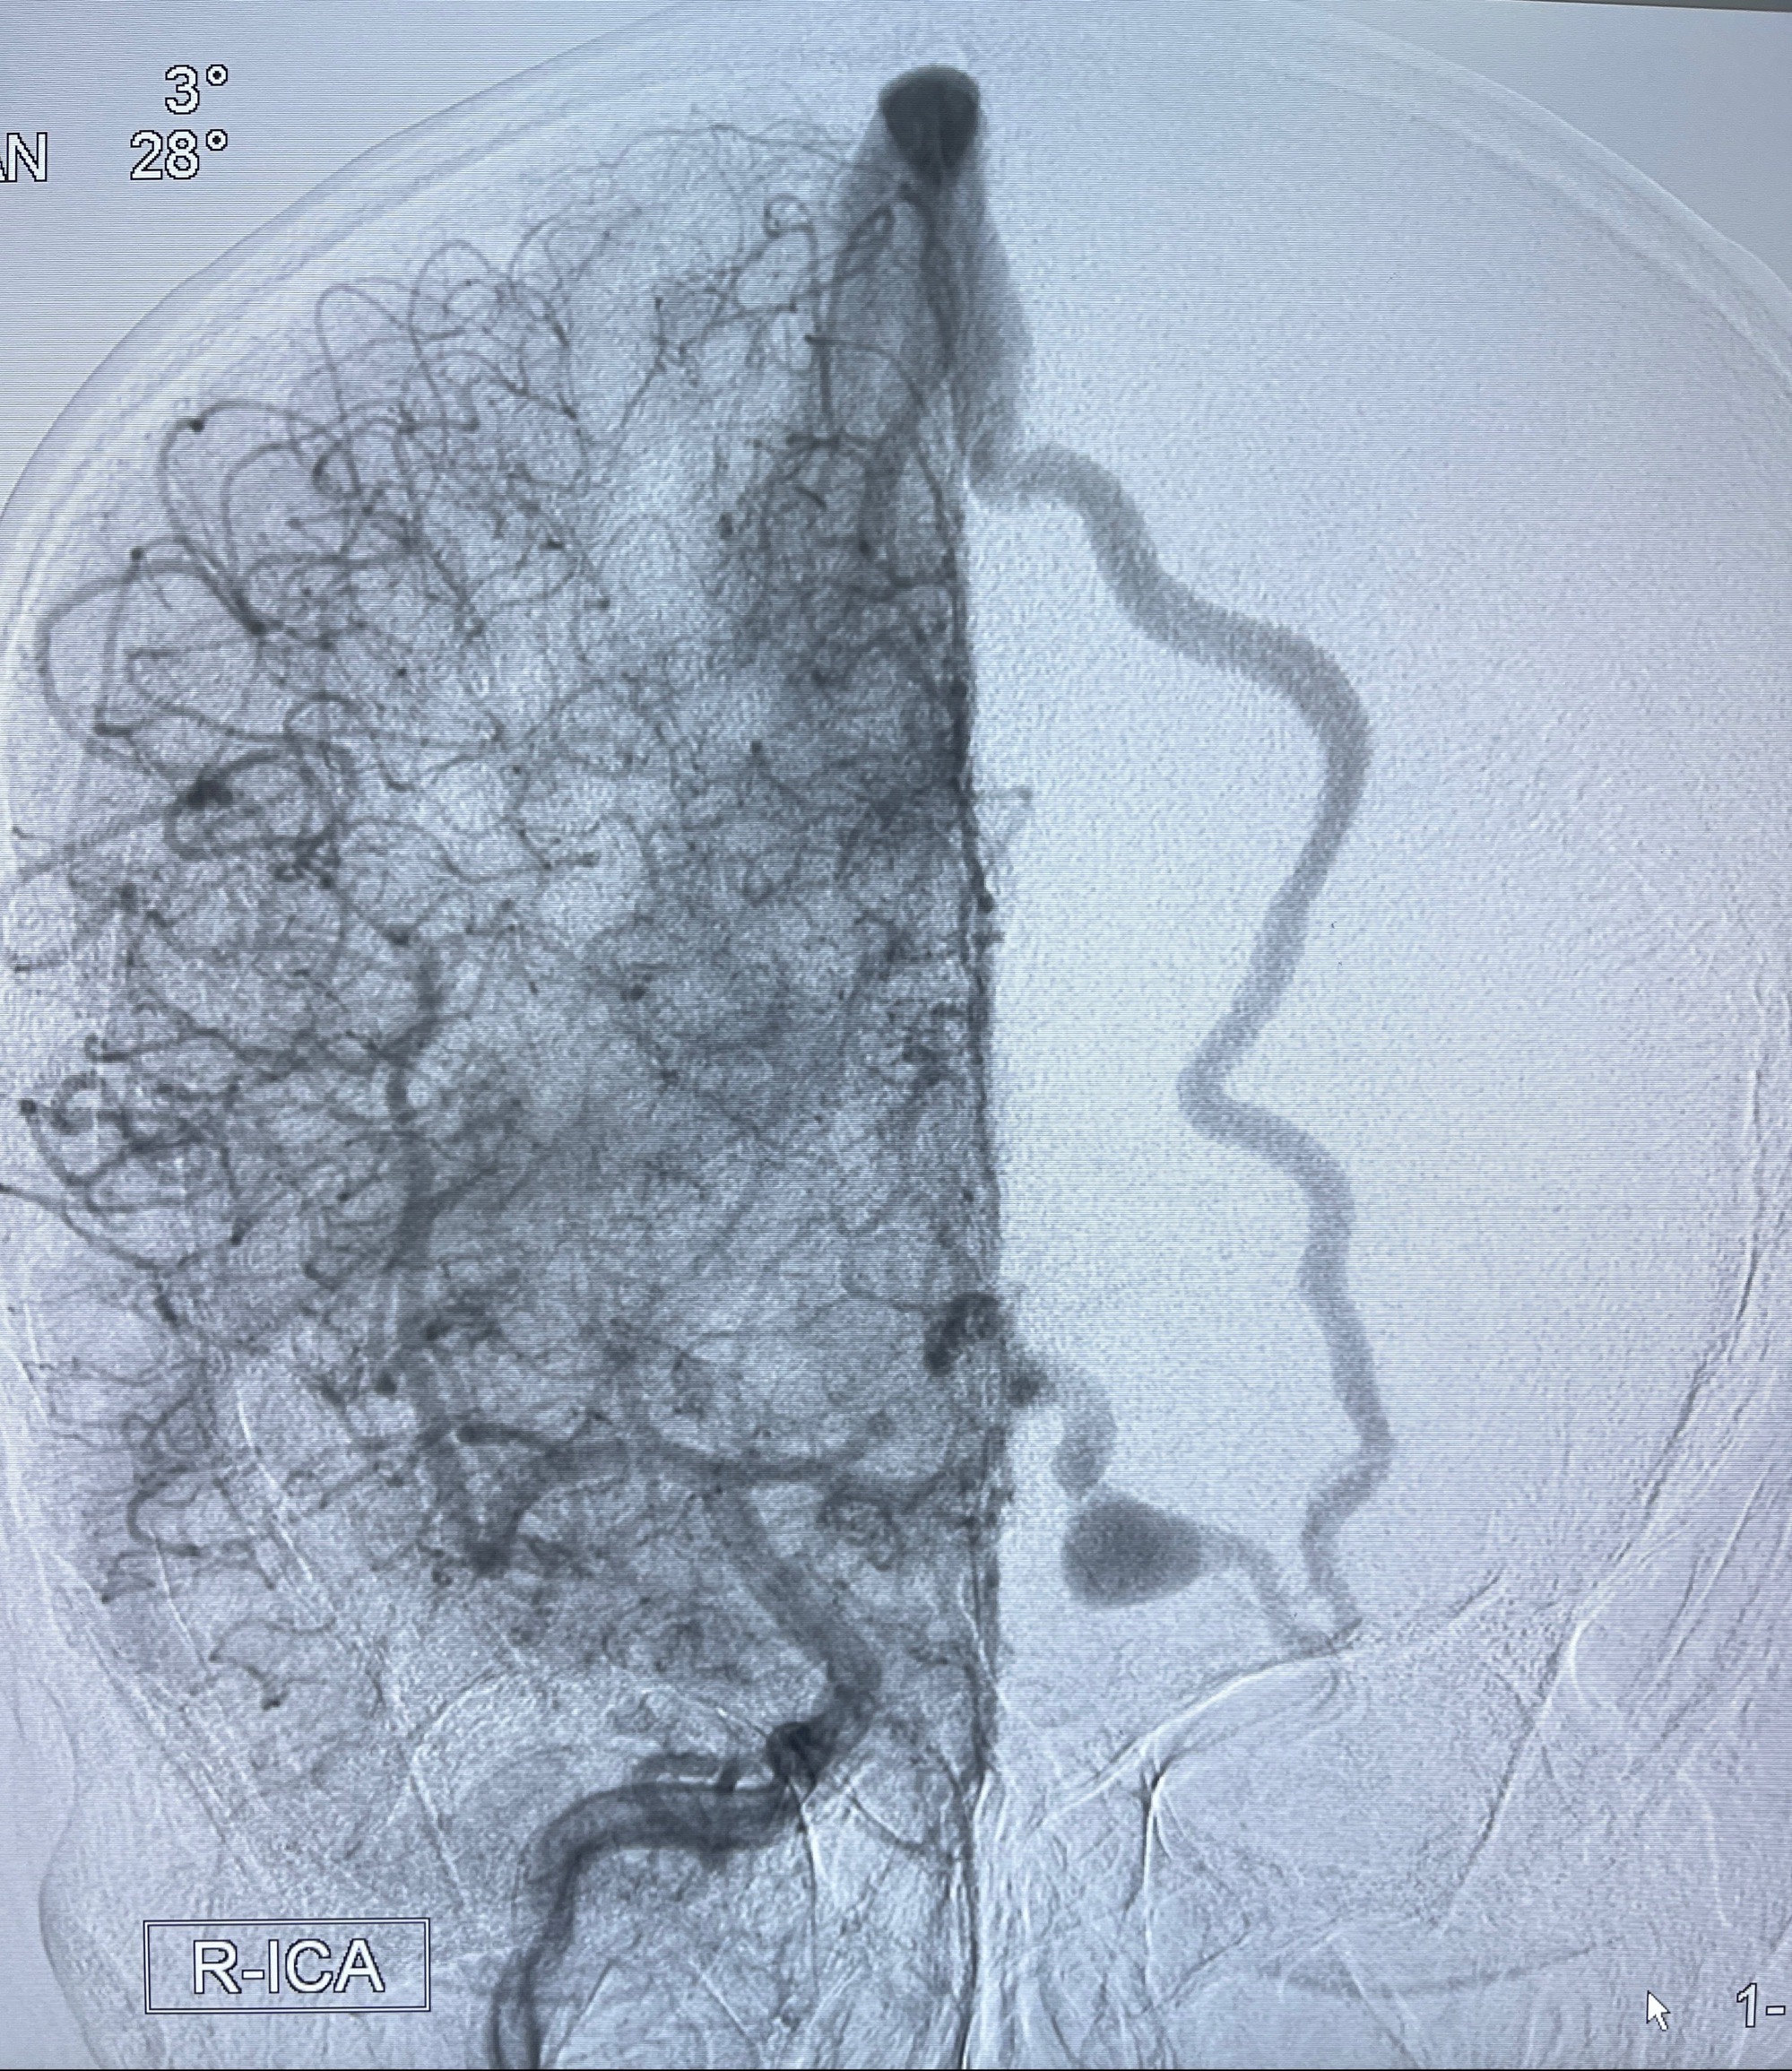

2023-09-13全脑血管造影:前颅底硬脑膜动静脉瘘,供血动脉为双侧胼周动脉、眼动脉脑膜支,静脉向上矢状窦方向引流

治疗策略:

- 外科手术?

- 介入干预:静脉途径栓塞or动脉途径填塞?